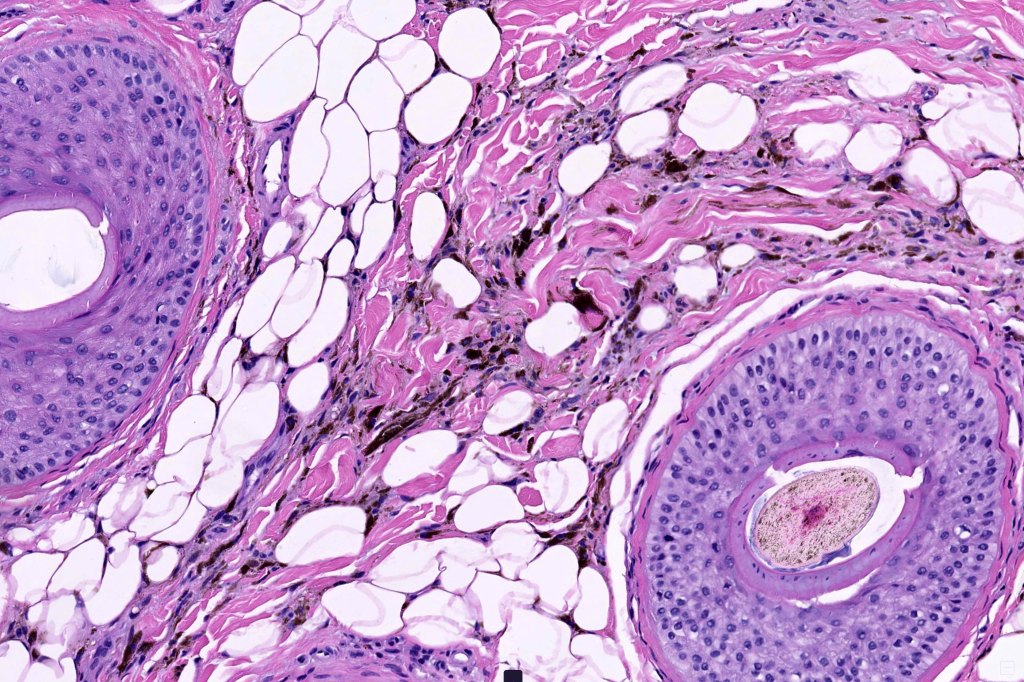

- Melanoma arising in a pre-existent blue nevus (common or more often cellular) or denritic melanocytosis including nevus of Ota, Ita & pilar neurocristic hamtoma

•Develops within a precursor lesion as one or more nodules of epithelioid or spindled cell melanoma

Melanoma arising in a pliar neurocristic hamartoma